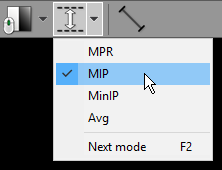

Alternatively, these modes are available from the Thickness drop-down menu.